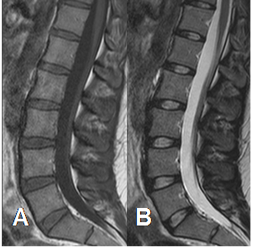

Fig 5. Medula ósea roja normal en adulto.

A: RM sagital en T1 y B: RM sagital en T2. Medula roja con señal intermedia en ambas secuencias.